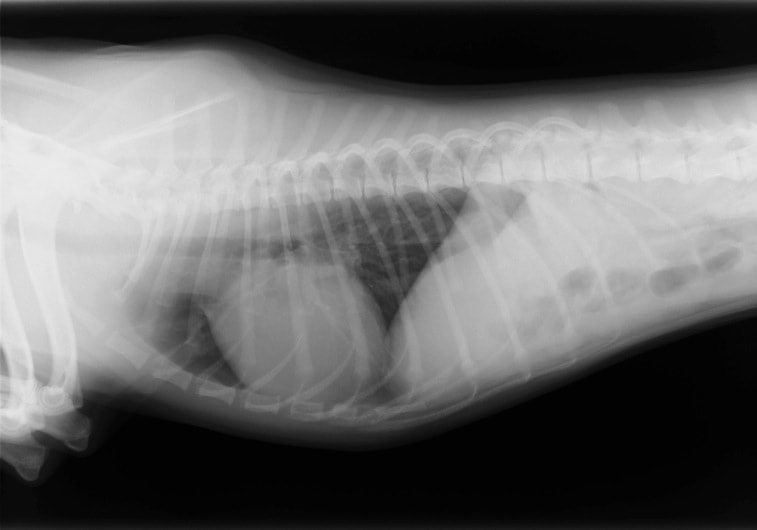

症例6:【ACVIM StageD ビーグル 10歳 去勢雄】

A:胸部レントゲン写真 側面像

左側胸壁心尖部領域を最強点とするLevine 5/6の収縮期性心雑音が聴取された。安静時にも咳が認められる。胸部レントゲン検査において重度の心拡大が及び肺水腫が認められた。超音波検査では、重度の僧帽弁閉鎖不全、三尖弁閉鎖不全が認められた。三尖弁逆流速度から肺高血圧症が示唆された。ACE阻害薬、ピモベンダン、硝酸イソソルビド徐放剤、ベラプロストナトリウム、利尿剤としてフロセミド及びスピロノラクトンを用いて治療を行っている。